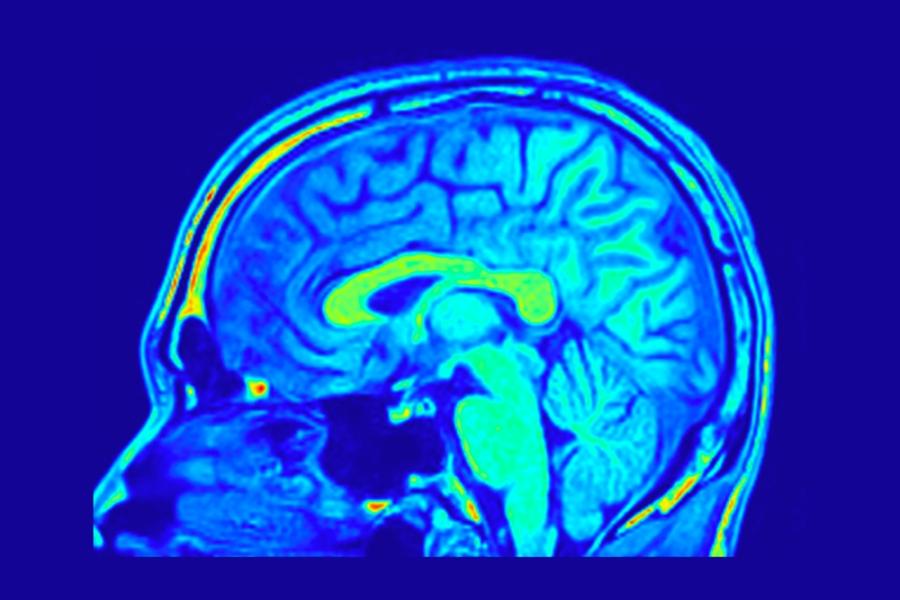

Те са анализирали над 2600 ядрено-магнитни изображения на мозъка на хора на възраст между 30 и 97 години, проследявайки как структурата и формата на мозъка се изменят с възрастта и как тези промени се свързват с резултатите от когнитивни тестове.

Според изследователите мозъкът не се променя равномерно — докато някои области се свиват, други се разширяват. При хора с признаци на когнитивен спад тези деформации се оказват по-изразени.

Учените обръщат специално внимание на енториналния кортекс – зона, която регулира паметта и е една от първите, засегнати при болестта на Алцхаймер.

Според тях възрастовите промени във формата на мозъка могат да създадат механичен натиск върху тази уязвима област, което улеснява натрупването на токсични протеини и увреждането на нервните клетки.